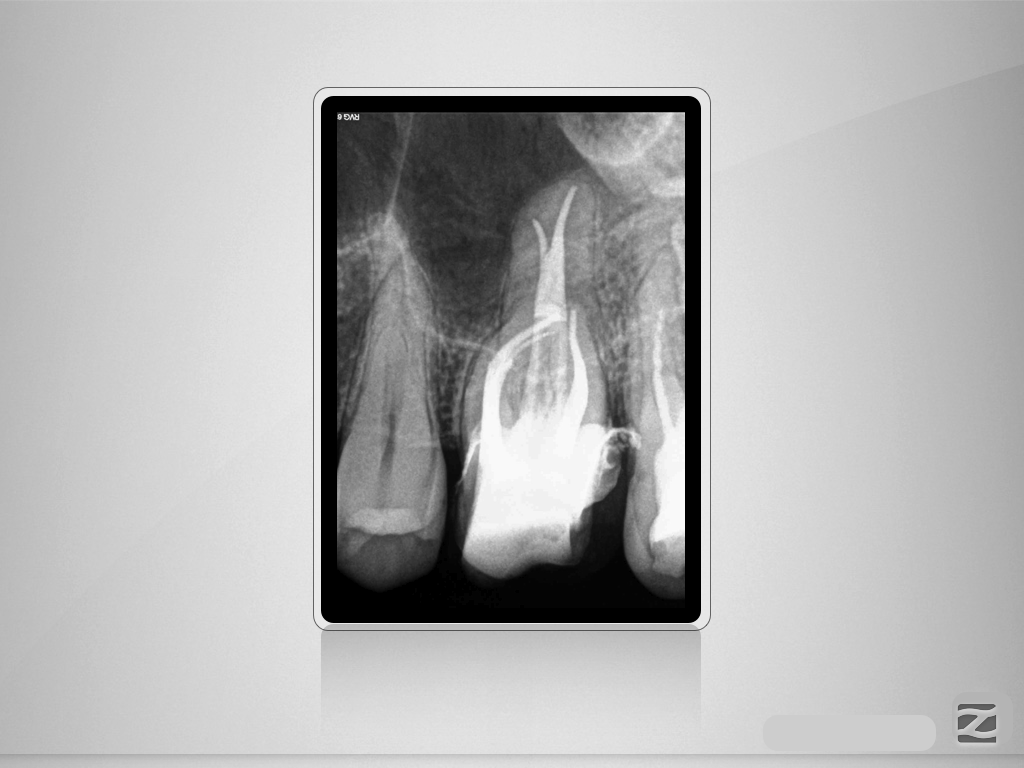

26D.005

Unerwartetes